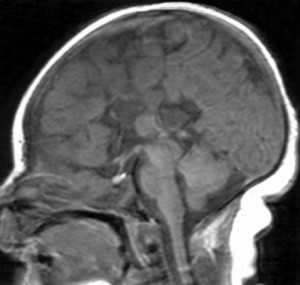

МРТ. Т1-зависмая сагиттальная томограмма. Синдром Экарди.

Кроме того полимикрогирия может входить в состав синдром Экарди (Aicardi) -Х-связанной доминантной патологией. Он протекает в виде спазмов и хориоретинопатии. При МРТ часто выявляются гипоплазия мозжечка, агенезия или недоразвитие мозолистого тела, кисты ЗЧЯ и средней линии, папилломы сосудистого сплетения.